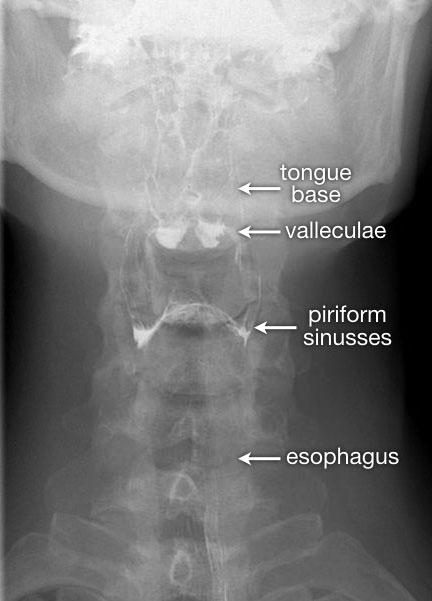

Tư thế thẳng (AP-view) quan trọng để đánh giá sự bất đối xứng.

TRÁI: Tư thế nghiêng khi bệnh nhân phát âm “aaa”. Xương móng (H) và nền lưỡi (T) di chuyển ra trước. Xoang hình lê trái và phải được chiếu chồng lên nhau. Đầu mút của màn hầu (SP) được quan sát thấy. PHẢI: Các hố lưỡi-thanh thiệt (V) và xoang hình lê (P).

Hình ảnh đối quang kép của hầu họng

Đối với tư thế nghiêng, yêu cầu bệnh nhân phát âm “aaa”, vì điều này sẽ đưa lưỡi về phía trước và cho phép quan sát tốt hơn vùng hầu miệng và hạ hầu.

Trong tiếng Hà Lan, đây là chữ “eee”, vì được phát âm tương tự như “aaa” trong tiếng Anh.

Đối với tư thế AP, nghiệm pháp Valsalva cải tiến được thực hiện.

Bệnh nhân phải thổi hơi qua môi mím chặt như khi thổi kèn trumpet, đồng thời thư giãn vùng cổ.

Luôn thực hành nghiệm pháp này trước khi thăm khám để bệnh nhân biết cách thực hiện.

Bên trái là hình ảnh đối quang kép của hầu họng.

Sự phồng ra của thành bên hầu họng là bình thường và có thể khá rõ rệt (như trường hợp Dizzy Gillespie).

Những cấu trúc này được gọi là ‘tai hầu bên’ (lateral pharyngeal ears).